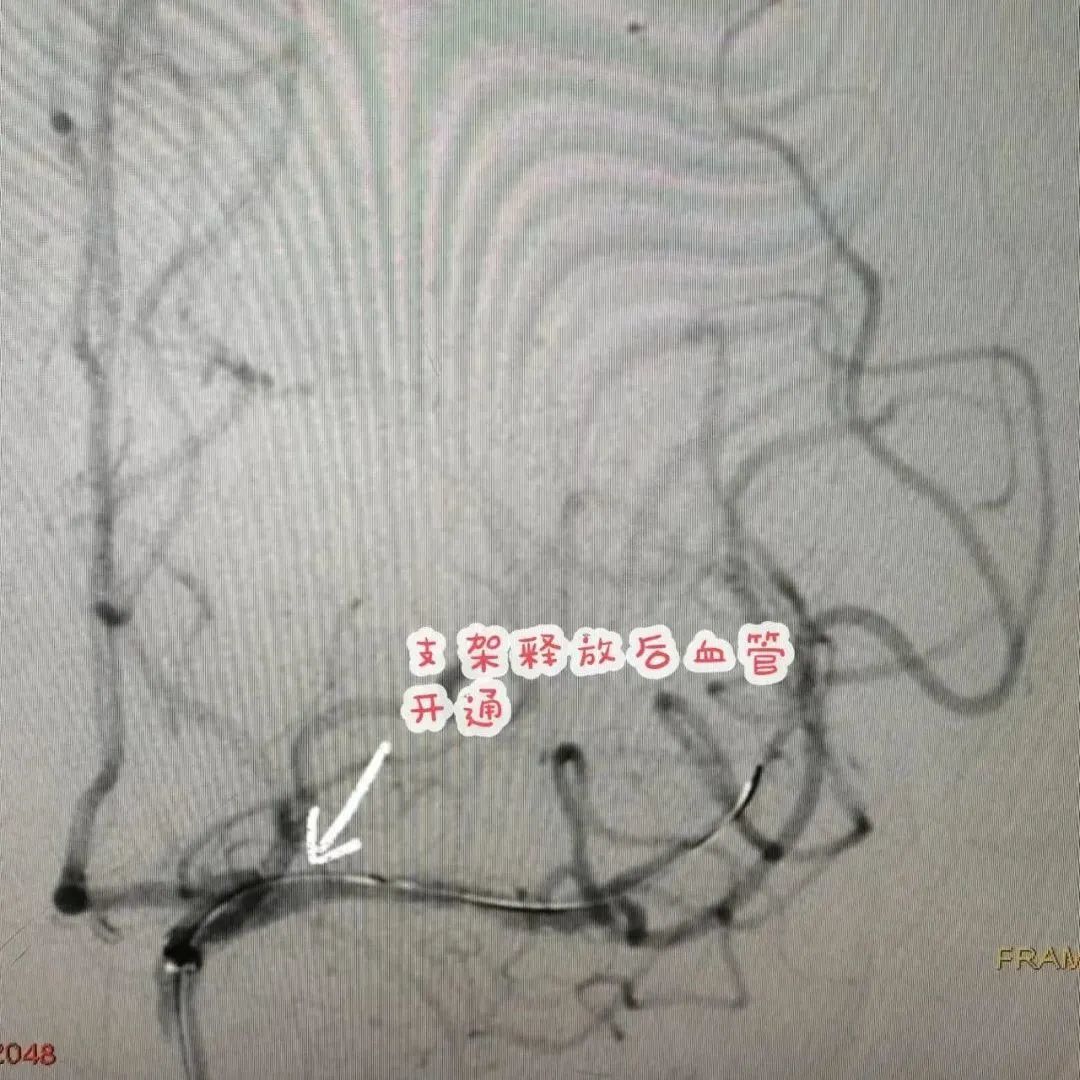

经神经内科介入团队对患者治疗方案综合评估,决定实施大脑中动脉闭塞开通术,这是治疗该患者的最佳方案。针对患者病情制定了详细的个性化手术流程和应急预案,确保患者安全。与患者家属积极沟通并取得同意后于4月8日,在全麻下行左侧大脑中动脉闭塞开通术。术后患者病情明显好转,已恢复正常并出院。

据了解,颅内动脉慢性闭塞开通术是目前我国神内介入的“天花板”,风险极大,随时可能出现高灌注等严重并发症危及患者生命。李先生通过此项技术治疗,成功消除大脑中动脉闭塞,较好改善大脑中动脉血管供血区域脑组织血流灌注,缓解了头晕、肢体无力认知功能障碍等症状,为李先生日后的健康生活扫除雷区。